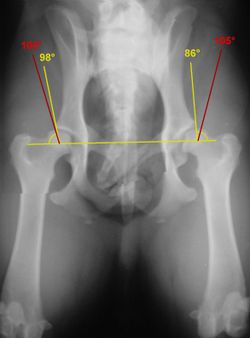

RöntgenEine zuverlässige Möglichkeit zum Erkennen des Schweregrades der Erkrankung bildet die Röntgenuntersuchung. Da bei dieser die Gelenke überstreckt werden müssen, was beim Vorliegen einer HD starke Schmerzen verursacht, wird sie unter einer Kurznarkose durchgeführt. Voraussetzung für eine aussagekräftige Diagnose ist die exakte Positionierung des untersuchten Tieres in Rückenlage mit gestreckten, parallel gelagerten Oberschenkeln und orthograd zum Strahlengang eingedrehten Kniescheiben. Zusätzliche Aufnahmen können in "Froschhaltung" der Oberschenkel oder im seitlichen (latero-lateralen) Strahlengang erfolgen.Röntgenaufnahme einer HD beim Hund. Der Femurkopf ist bereits subluxiert, das Acetabulum (Hüftgelenkspfanne) umgreift ihn nicht mehr (rote Pfeile). Die Femurköpfe zeigen bereits Abweichungen von der Halbkugelform (gelbe Pfeile); rechts im Bild sind deutliche arthrotische Veränderungen des Femurkopfes erkennbar. Anwendung des Norberg-Winkels zur Abschätzung des Schweregrades einer Hüftgelenksdysplasie(englische Bulldogge). Die roten Schenkel geben den minimalen Grenzwert für HD-Freiheit, die gelben Schenkel den tatsächlichen Winkel an. |

| Ein wesentliches Auswertungskriterium ist der Norberg-Winkel. Er ist als der Winkel definiert, der zwischen dem Zentrum des Oberschenkelkopfes und dem vorderen Pfannenrand abgetragen wird (siehe Abbildung). Bei einem HD-freien Tier sollte er mehr als 105° betragen (rote Linien). Weitere Kriterien zur Beurteilung sind die Kongruenz von Oberschenkelkopf und Gelenkpfanne, die Weite des Gelenkspaltes, die Pfannenkontur, die Kontur des Oberschenkelkopfes sowie das Vorhandensein von Hinweisen auf arthrotische Prozesse wie walzenförmige Verdickungen des Oberschenkelhalses, Randwülste an der Gelenkpfanne, unter dem Knorpel befindliche Verdichtungen der Knochensubstanz im Pfannenbereich und die Einlagerung von Knochenmaterial am Ansatz der Gelenkkapsel (Morgan-Linie). Die züchterische Auswertung von HD-Aufnahmen ist nur von zugelassenen Gutachtern möglich, an die der Tierarzt die Röntgenbilder einschickt. |